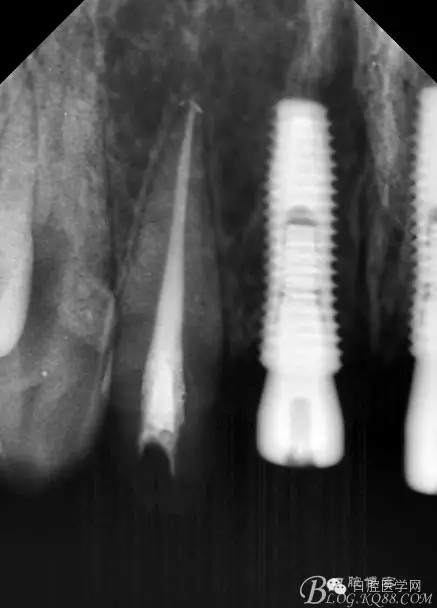

設計方案:11.21種植(選用登騰系統(tǒng),GBR植骨)12.22 RCT后樁冠修復,牙齦瓷修復。

一期手術后3-6個月可做二次修復,接愈合基臺,拆線后10-15天根據(jù)情況可以采模型做牙冠。